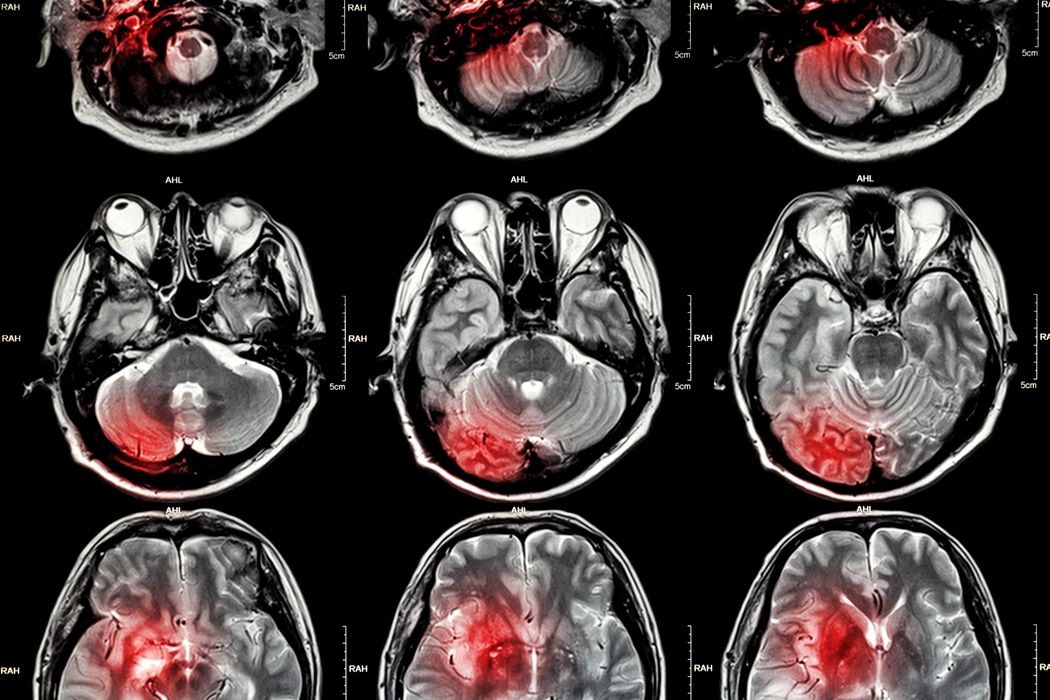

Un antidepresiv ar putea trata tumorile cerebrale

Glioblastomul este o tumoare cerebrală deosebit de agresivă, care în prezent este incurabilă. Medicii oncologi pot prelungi speranța de viață a pacienților prin operații, radioterapie, chimioterapie sau intervenții chirurgicale. Cu toate acestea, jumătate dintre pacienți […]